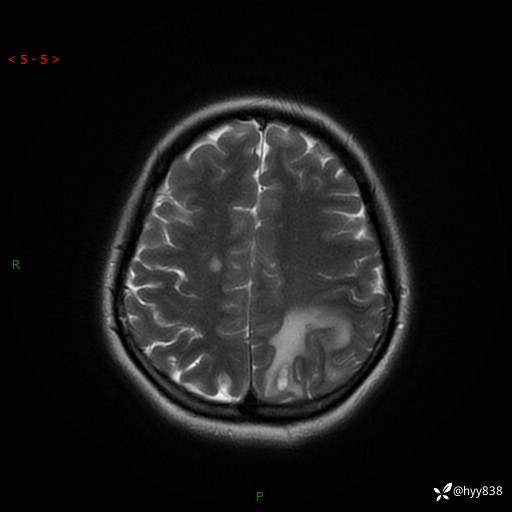

颅脑MRI平扫+增强